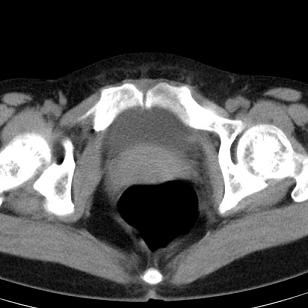

标题: CT19559:子宫及附件正常吗?

女,35岁,反复下腹部隐痛数月。

感觉上,子宫好象大了点

如果未孕,子宫体稍大,宫腔增宽,附件区未见异常密度影,还是建议结合b超检查为好,ct平扫对妇科没有优势。

子宫弥漫性等密度肿大,宫腔内缘见结节影突入腔内,子宫内膜异位可能